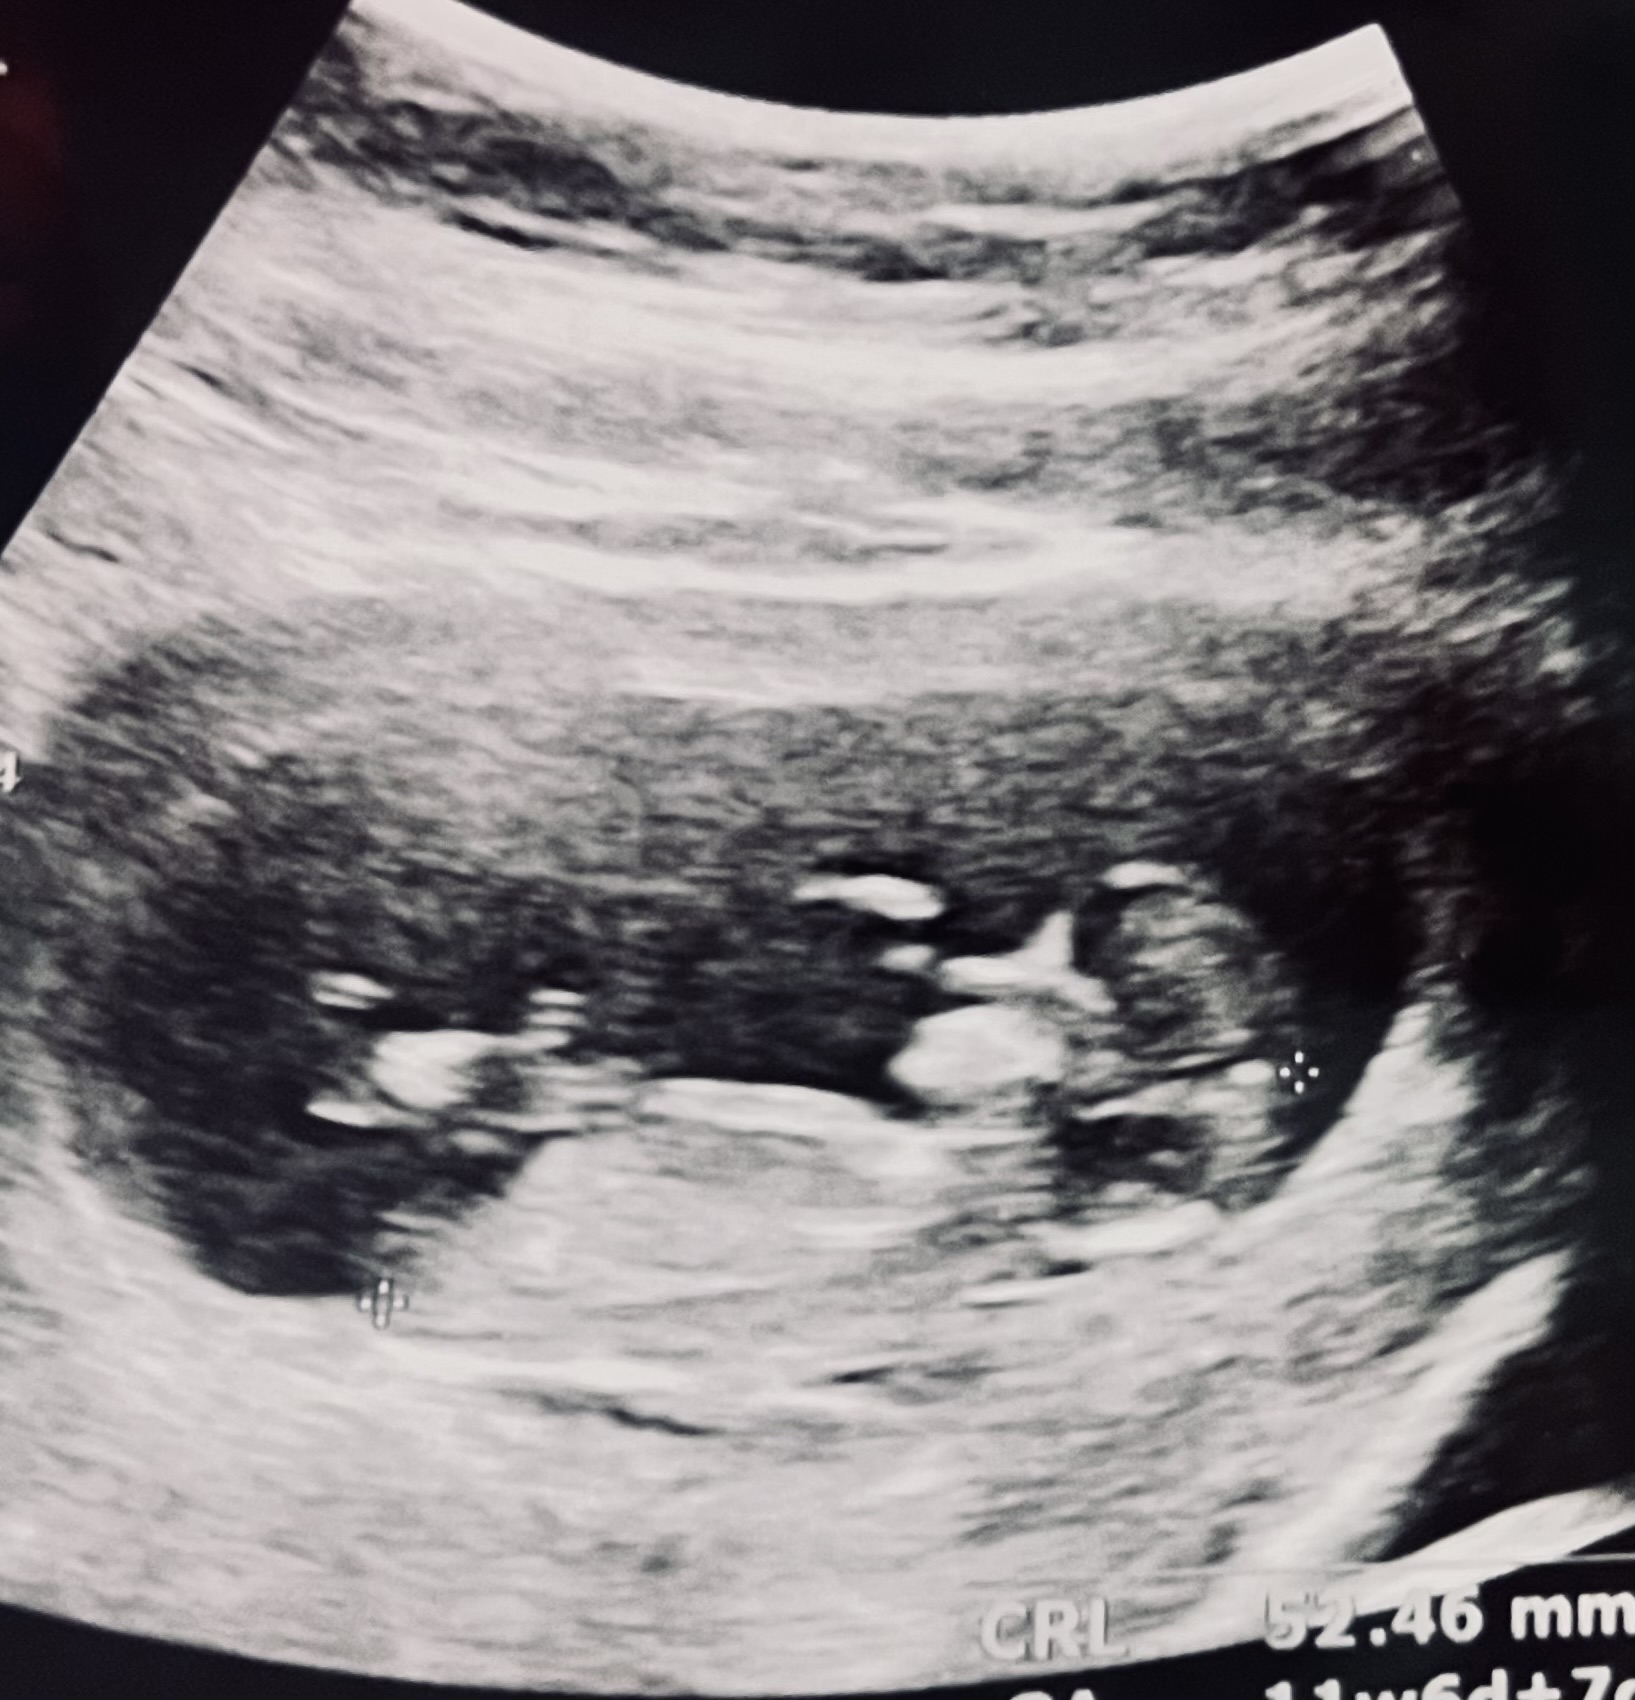

تعداد رای : 13

نظرسنجی

دختر

3

23%

پسر

6

46%

هنوز زوده

1

7%

معلوم نیست